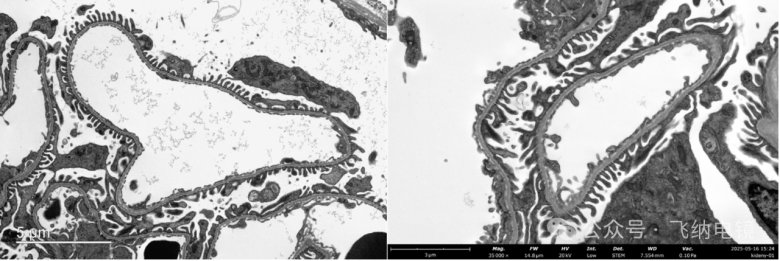

03組織切片——鼻粘膜上皮細胞

左:TEM;右:Pharos STEM